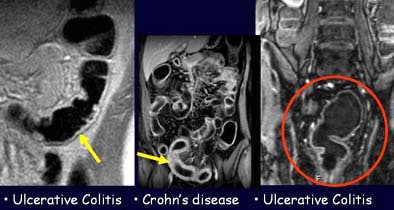

![]() |

| The patient on the right is affected by ulcerative colitis, seen as a pattern of moderate colonic wall thickening and enhancement limited to the inner layer of the colon wall. The same pattern is present in the patient on the left side, who was diagnosed with ulcerative colitis involving the rectum. The patient in the middle is affected by Crohn's disease, and presents with more conspicuous thickening of the colonic wall and a transmural enhancement pattern. Images courtesy of Dr. Pasquale Paolantonio. |